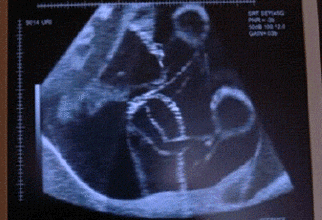

测胎心动的时候,超过140的话,男孩多些,小于140的话,女孩多些。胎动次数的多少、快慢、强弱等,常表示着胎儿的安危,因此,人们把胎动称为胎儿安危的标志。胎动正常,表示胎盘功能良好,输送给胎儿的氧气充足,胎儿在子宫内发育健全。小生命在子宫内愉快地生存着。据妇产科专家观测,正常明显胎动不少于每小时3~5次;12小时明显胎动次数约30~40次以上。但由于胎儿个体差异不同,有的胎儿在12小时内胎动次数可达100次以上。但只要胎动有规律,有节奏,变化不大,都说明胎儿发育是正常的。